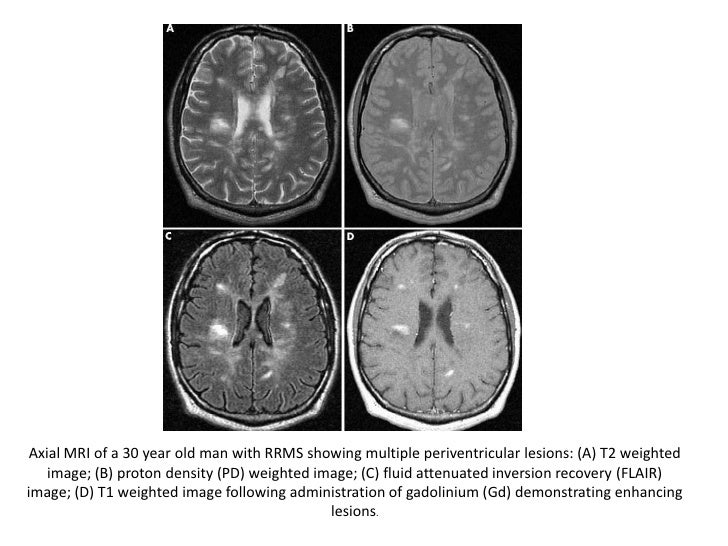

Az MRI egy agyi képalkotó eljárás, ami az agy szerkezetéről és annak eltéréseiről nyújt információt. A vizsgálat elve, hogy a fej körüli változó mágneses tér hatására az agy folyadékrészecskéi egymástól eltérő módon rendeződnek. A gép a rendeződés idejét és egyéb paramétereit méri és alakítja át képi információvá.